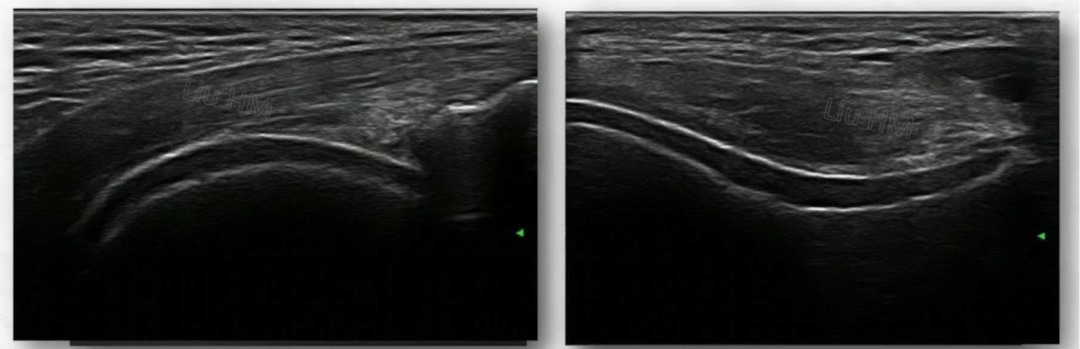

痛风性关节炎

(髌上囊滑膜炎、积液、点线样强回声,关节软骨面“双轨征”)

类风湿关节炎

(腕关节滑膜增厚,血管翳形成,关节软骨面不光滑,骨皮质呈虫蚀状破坏)